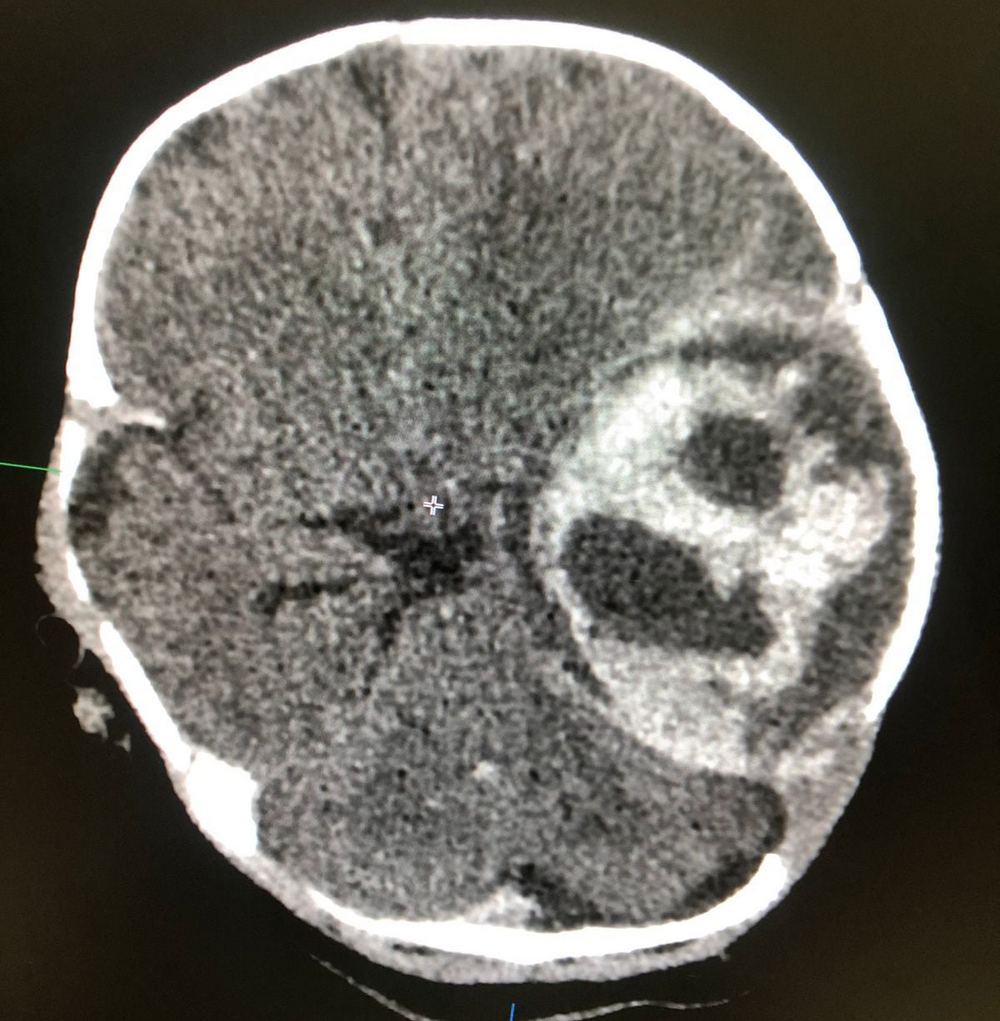

Фото предоставили в областной детской больнице

В приёмный покой областной детской больницы в экстренном порядке 21 октября поступил ребёнок в возрасте 38 дней. Его сразу же направили в отделение реанимации с диагнозом: острое нарушение мозгового кровообращения (ОНМК, инсульт), внутримозговая гематома, дислокационный синдром, постгеморрагическая анемия тяжелой степени, ДВС-синдром (синдром диссеминированного внутрисосудистого свёртывания) и кома I-степени.

Была проведена декомпрессионная трепанация черепа и удалены внутримозговые гематомы.